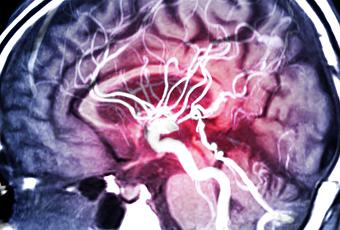

Vers un nouveau mode de prise en charge de l'AVC ? Les images du cerveau des patients montrent que la taille des dommages de l'AVC est considérablement réduite avec le nérinétide.